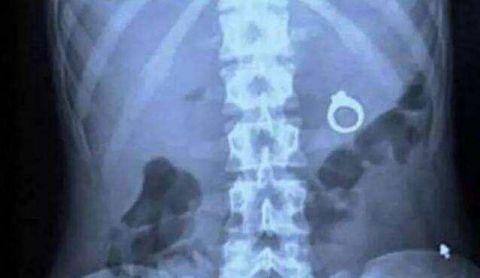

一只混在蛋糕里面的戒指被一起吃下去了